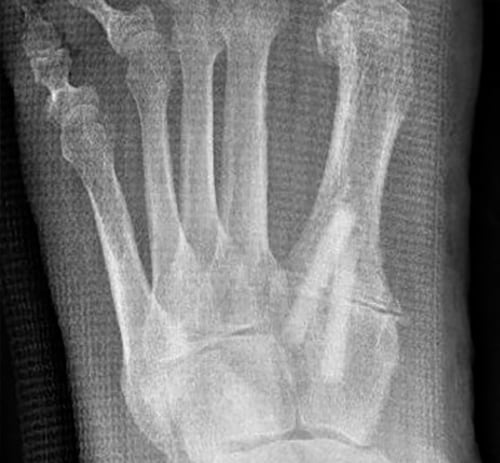

6 weeks postoperatively

Beginning to build through the osteotomy

6 months postoperatively

Bone screw grafts partially remodeled into own bone